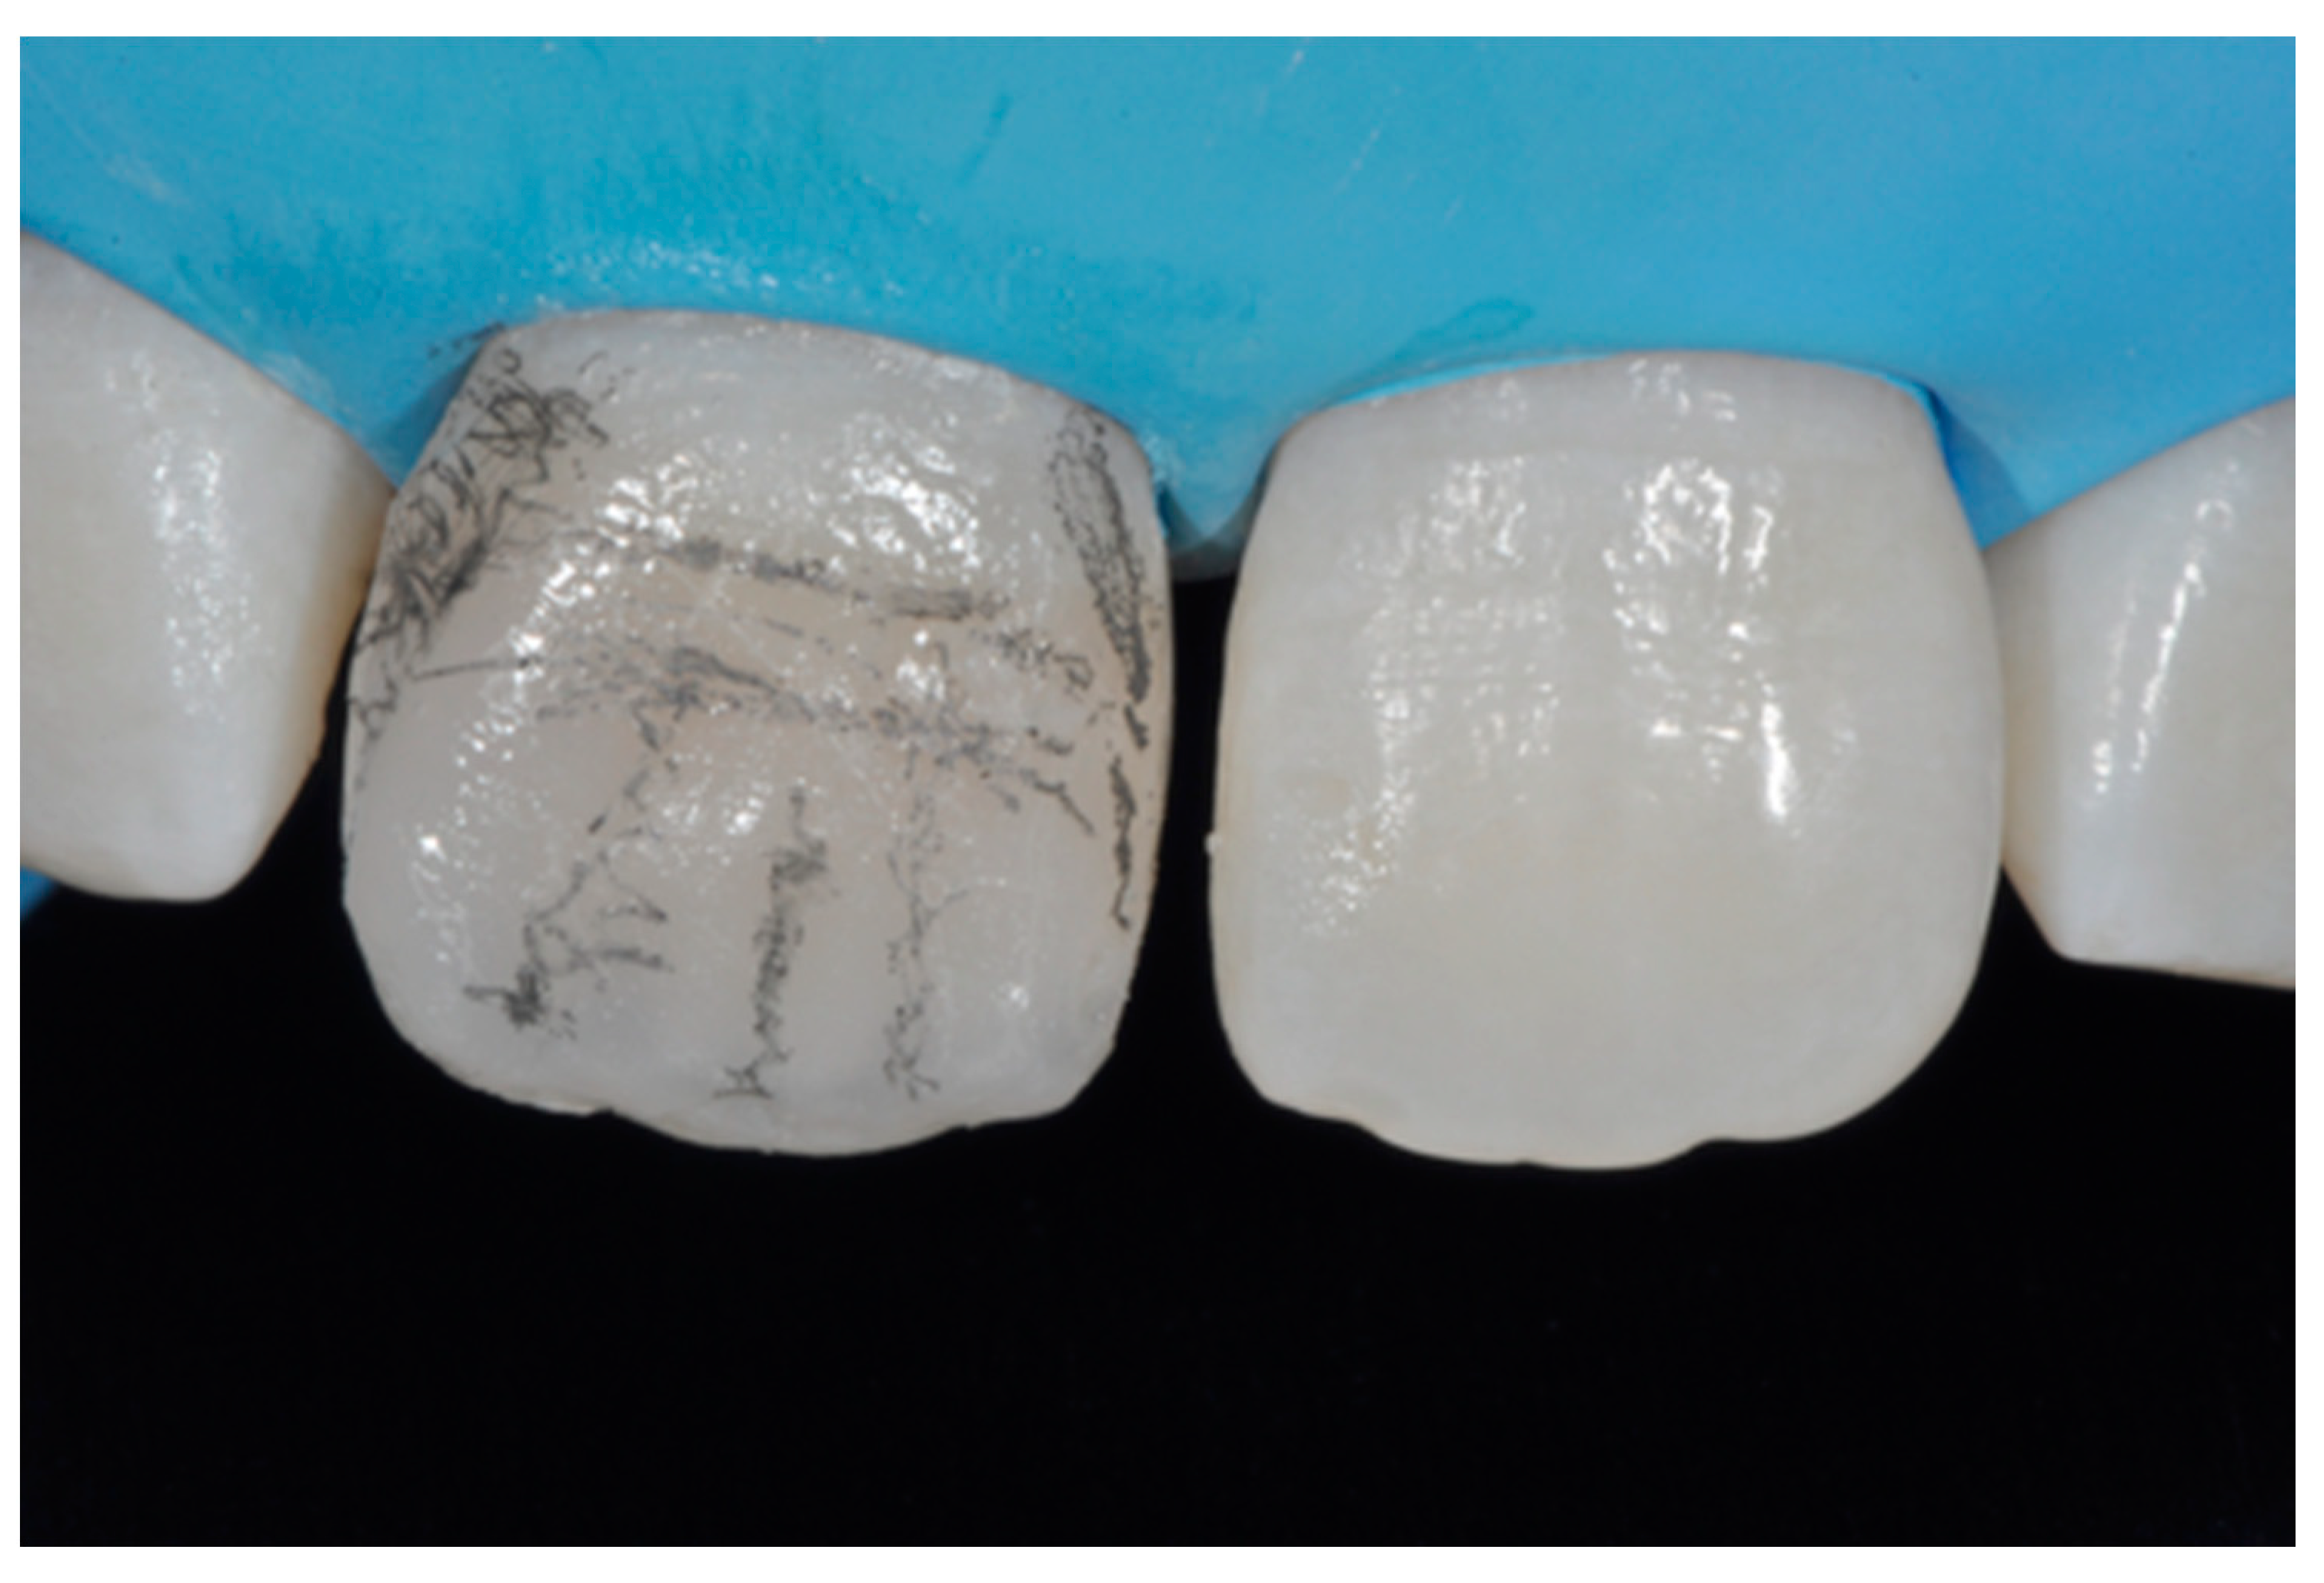

Finishing and polishing procedures were performed with a diamond bur (WL 268 014 Horico, Berlin, Germany), silicone points (Identoflex, Kerr, Bioggio, Switzerland) brushes (Jiffy Goat Air Brushes, Ultradent Products, South Jordan, UT, USA), and diamond pastes (Diamond Polish Mint, Ultradent Products, South Jordan, UT, USA) (Figure 13 and Figure 14). Satisfactory clinical and radiographic outcome was considered satisfactory at 3-months, 1-year, and 5-years post-operative (Figure 15, Figure 16, Figure 17, Figure 18 and Figure 19).

Figure 13.

Vertical and horizontal anatomy outlined with a pencil. Reprinted from Restauri diretti nei settori anteriori, G. Paolone, S. Scolavino, © 2021, with permission from Quintessence Publishing Italy.